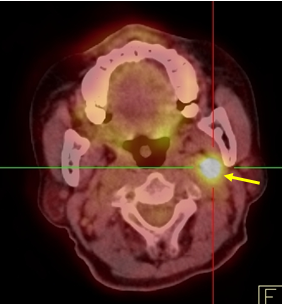

Hình 2 ghi lại kết quả chụp PET/CT của bệnh nhân Trịnh Th. T. L., nữ, 66 tuổi, gần đây thấy xuất hiện ù tai trái, hạch cổ trái. Sinh thiết hạch cổ trái là ung thư biểu mô di căn hạch chưa rõ nguyên phát. Bệnh nhân được chỉ định chụp PET/CT để tìm ổ ung thư nguyên phát.

Hình 2: Hình PET toàn thân và hình PET/CT thấy tổn thương ở vùng vòm (mũi tên đỏ) và hạch góc hàm (mũi tên xanh) tăng hấp thu FDG. Hình ảnh hướng đến ung thư vòm di căn hạch góc hàm trái. Bệnh nhân đi nội soi và bấm sinh thiết vùng vòm trái cho kết quả ung thư biểu mô tế bào vẩy.